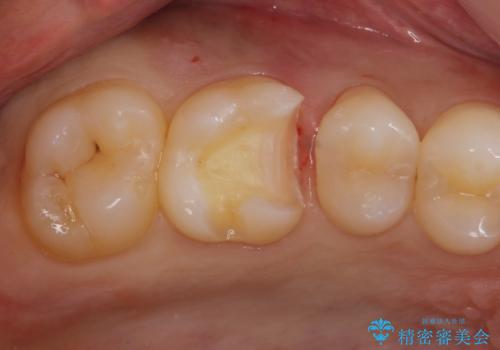

- 銀歯を白くしたいとの事で来院。

銀歯を除去し拡大鏡下でカリエスがない事を確認した後、e-maxインレーにて治療を行いました。